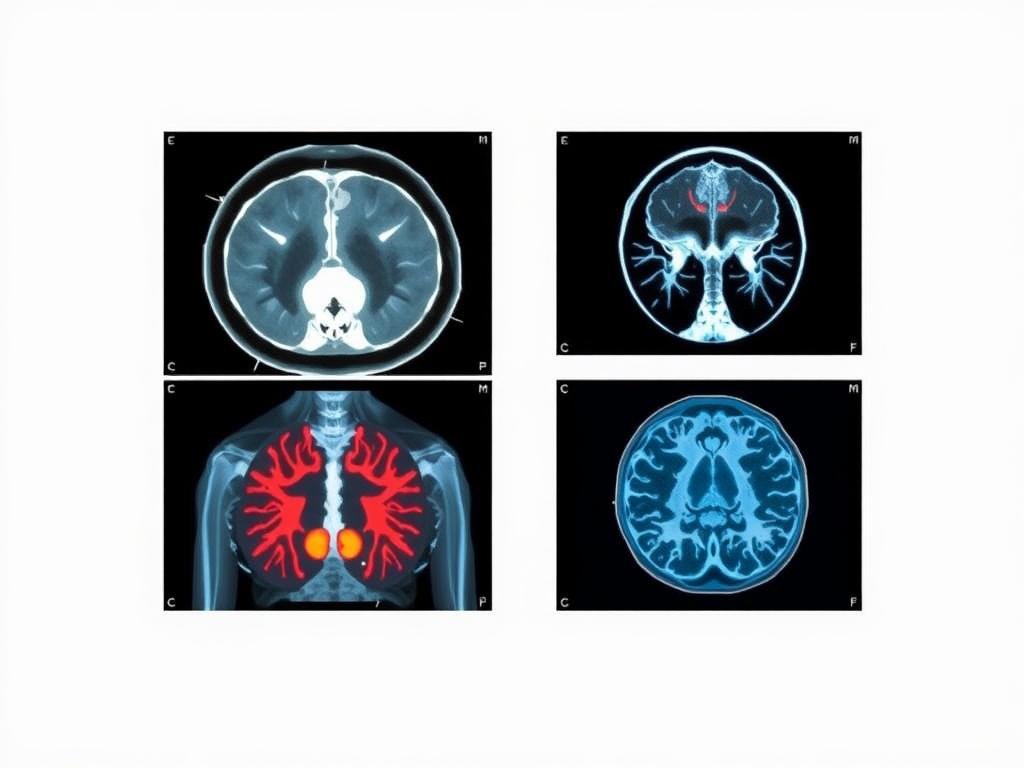

Атлас по лучевой диагностике — это не просто сборник изображений. Это систематизированная карта анатомии, нормальных вариантов и типичных патологических находок, с аннотациями и легендами. В современном формате атласы покрывают все ключевые направления: КТ-атласы, МРТ-атласы и рентген-атласы, а часто встречаются мультимодальные сборники, где одно и то же структурное образование представлено разными методами. Такой подход облегчает сопоставление признаков в разных режимах сканирования, что особенно полезно в сложных клинических случаях.

Сама идея объединения КТ, МРТ и рентгенологических снимков в одном атласе — это попытка выстроить единый язык восприятия анатомии и патологии. Когда вы смотрите на один и тот же участок тела под разными углами и последовательностями, становится понятнее, как меняются контуры тканей, как распознаются грандиозные различия между опухолевыми узлами, воспалением или дегенеративными изменениями. Именно поэтому многие обучающие курсы и клинические резюме идут параллельно с мультимодальными атласами, которые часто выпускаются именно в PDF-формате.